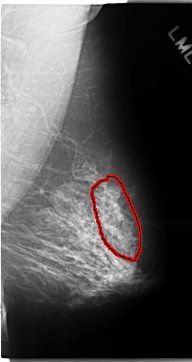

C_0133_1.LEFT_MLO

LEFT_MLO LINES 4704 PIXELS_PER_LINE 2488 BITS_PER_PIXEL 12 RESOLUTION 50 OVERLAY

FILE: C_0133_1.LEFT_MLO.OVERLAY

TOTAL_ABNORMALITIES 1

ABNORMALITY 1

LESION_TYPE CALCIFICATION TYPE AMORPHOUS DISTRIBUTION REGIONAL

ASSESSMENT 4

SUBTLETY 3

PATHOLOGY MALIGNANT

TOTAL_OUTLINES 1

BOUNDARY